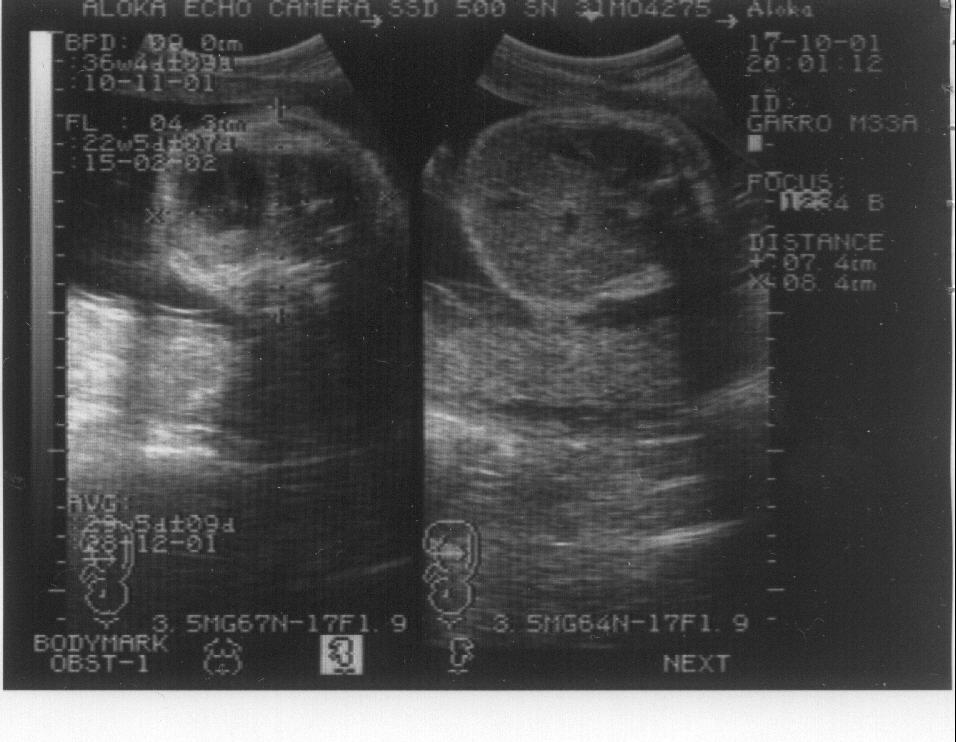

Un caso de osteogénesis imperfecta letal. Octavo mes de embarazo. Imagen 2/4

Imagen de la ecografía